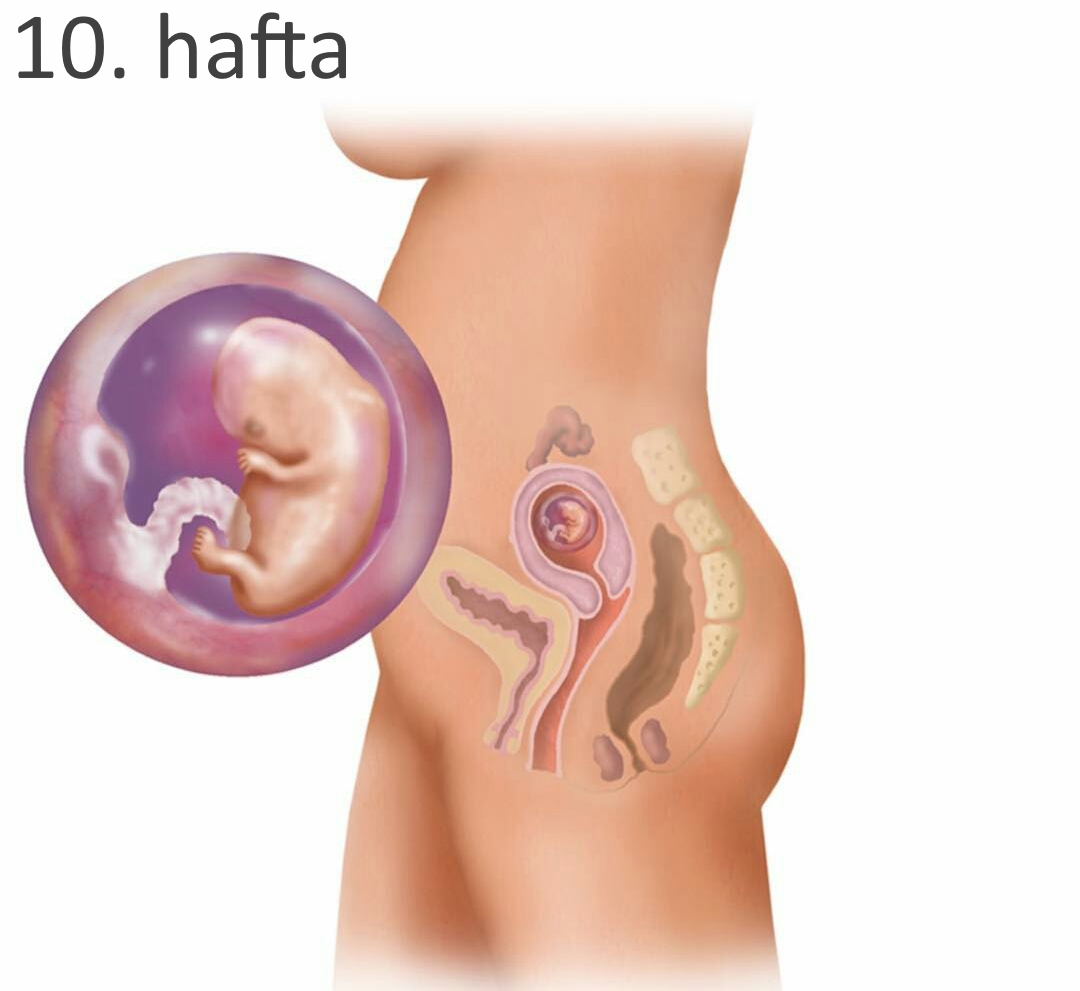

Ребёнок на 10 неделе беременности

Зародыш ребенка 10 недель

Зародыш на 10 неделе беременности

Ребёнок на 10 неделе беременности

Ребёнок на 10 неделе беременности

Зародыш человека 9-10 недель

Человеческий эмбрион 10 недель

Стадии развития эмбриона

Эмбрион на 10 неделе беременности

Малыш на 10 неделе беременности

Ребенок в животе по неделям